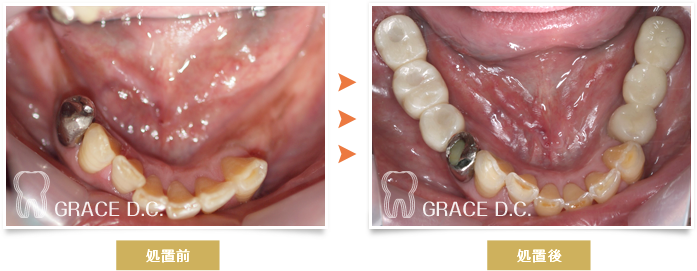

インプラント治療④

入れ歯が合わず噛めないとのことでご来院し、左右奥歯にインプラントを入れ修復した症例です。